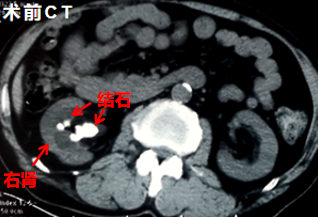

患者男性,61岁,主诉“发现左侧结石2月余”,既往有肾结石病史,近期复查发现右肾结石。入院腹部CT提示:右肾多发结石伴积水,右肾实质变薄,结石分别分布于肾盂、上组盏、肾中组(腹侧、背侧盏)、下组盏,盏颈狭窄,静脉肾盂造影显示右肾功能欠佳,为防止肾功能减退与病情进一步恶化,必须行手术治疗。

徐志强主任反复对患者进行查体,发现该患者结石多,直径大、位置复杂,盏颈狭窄,术中取石困难,术后结石残留率高。如采取传统单一的经皮肾镜手术方法需进行多次,且术中需要变换体位,势必会延长手术时间使手术风险加大。